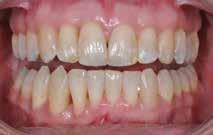

Den kliniske undersøgelse viser ingen symptomer fra muskler eller kæbeled. Ingen ledlyde ved åbne-/lukkebevægelse og ingen udsving ved åbne-/lukkebevægelse. Der er vertikalt overbid (VOB) 3-4 mm, horisontalt overbid (HOB) 1 mm, Angle kl. I med retroklination af såvel over- som underkæbeincisiver

A. Ortodontisk behandling med intrusion og proklination af underkæbefronten er simuleret med visualisering af slutresultatet. B-D. Nivellering af Spee kurve, type og position af attachments, biteramps på overkæbeincisiver til mild bidhævning, distorotation og distalisering af siderne i overkæben.

2. A. Orthodontic treatment with intrusion and proclination of the lower front simulated with visualisation. B-D. Leveling of the Spee curve, type and position of attachments, bite ramps on maxillary incisors for mild bite elevation, distorotation and distalization of the sides in the maxilla).

(Fig. 6 A-D). Relativt flad Spee kurve. Ud fra TWES 2.0 graduering har pt. slid af 2. grad i over- og underkæbefront, dog har 1-1 slid af 3. grad. Incisiverne har skarpe incisalkanter med emaljefrakturer og emaljeinfraktioner (Fig. 6 C, D) samt udtalte dentinkonkaviteter incisalt (Fig. 6 E). Posteriort ses slid af 1.-2. grad, og der er mistanke om natlig bruksisme, selvom patienten ikke oplyser dette. Der er såvel attrition som erosion med cuppings på flere molarer samt hævede fyldninger med mindre frakturer (Fig. 6 F, G). Erosiv årsag kan ikke identificeres ud fra kostanamnese. Der ses tydelige slidfacetter i hele tandsættet generelt. Patienten har perfekt mundhygiejne, ingen caries, slimhindeforandringer eller patologiske pocher.

Fig. 5. A, B. Smil og kæbeforhold før og efter. Et bredere smil med korrektion af de laterale mørke rum. C-F. Harmonisk hældning af overkæbe- og underkæbeincisiver, rekonstruktion af den tabte tandsubstans efter nivellering af gingivaniveau og optimal bukko-lingval placering til direkte plastbehandling.

5. A, B. Smile and jaw relationships before and after. A wider smile with correction of the lateral dark spaces. C-F. Harmonious inclination of the upper and lower jaw incisors, reconstruction of the lost tooth substance after leveling the gingival level, and optimal bucco-lingual positioning for direct plastic treatment.